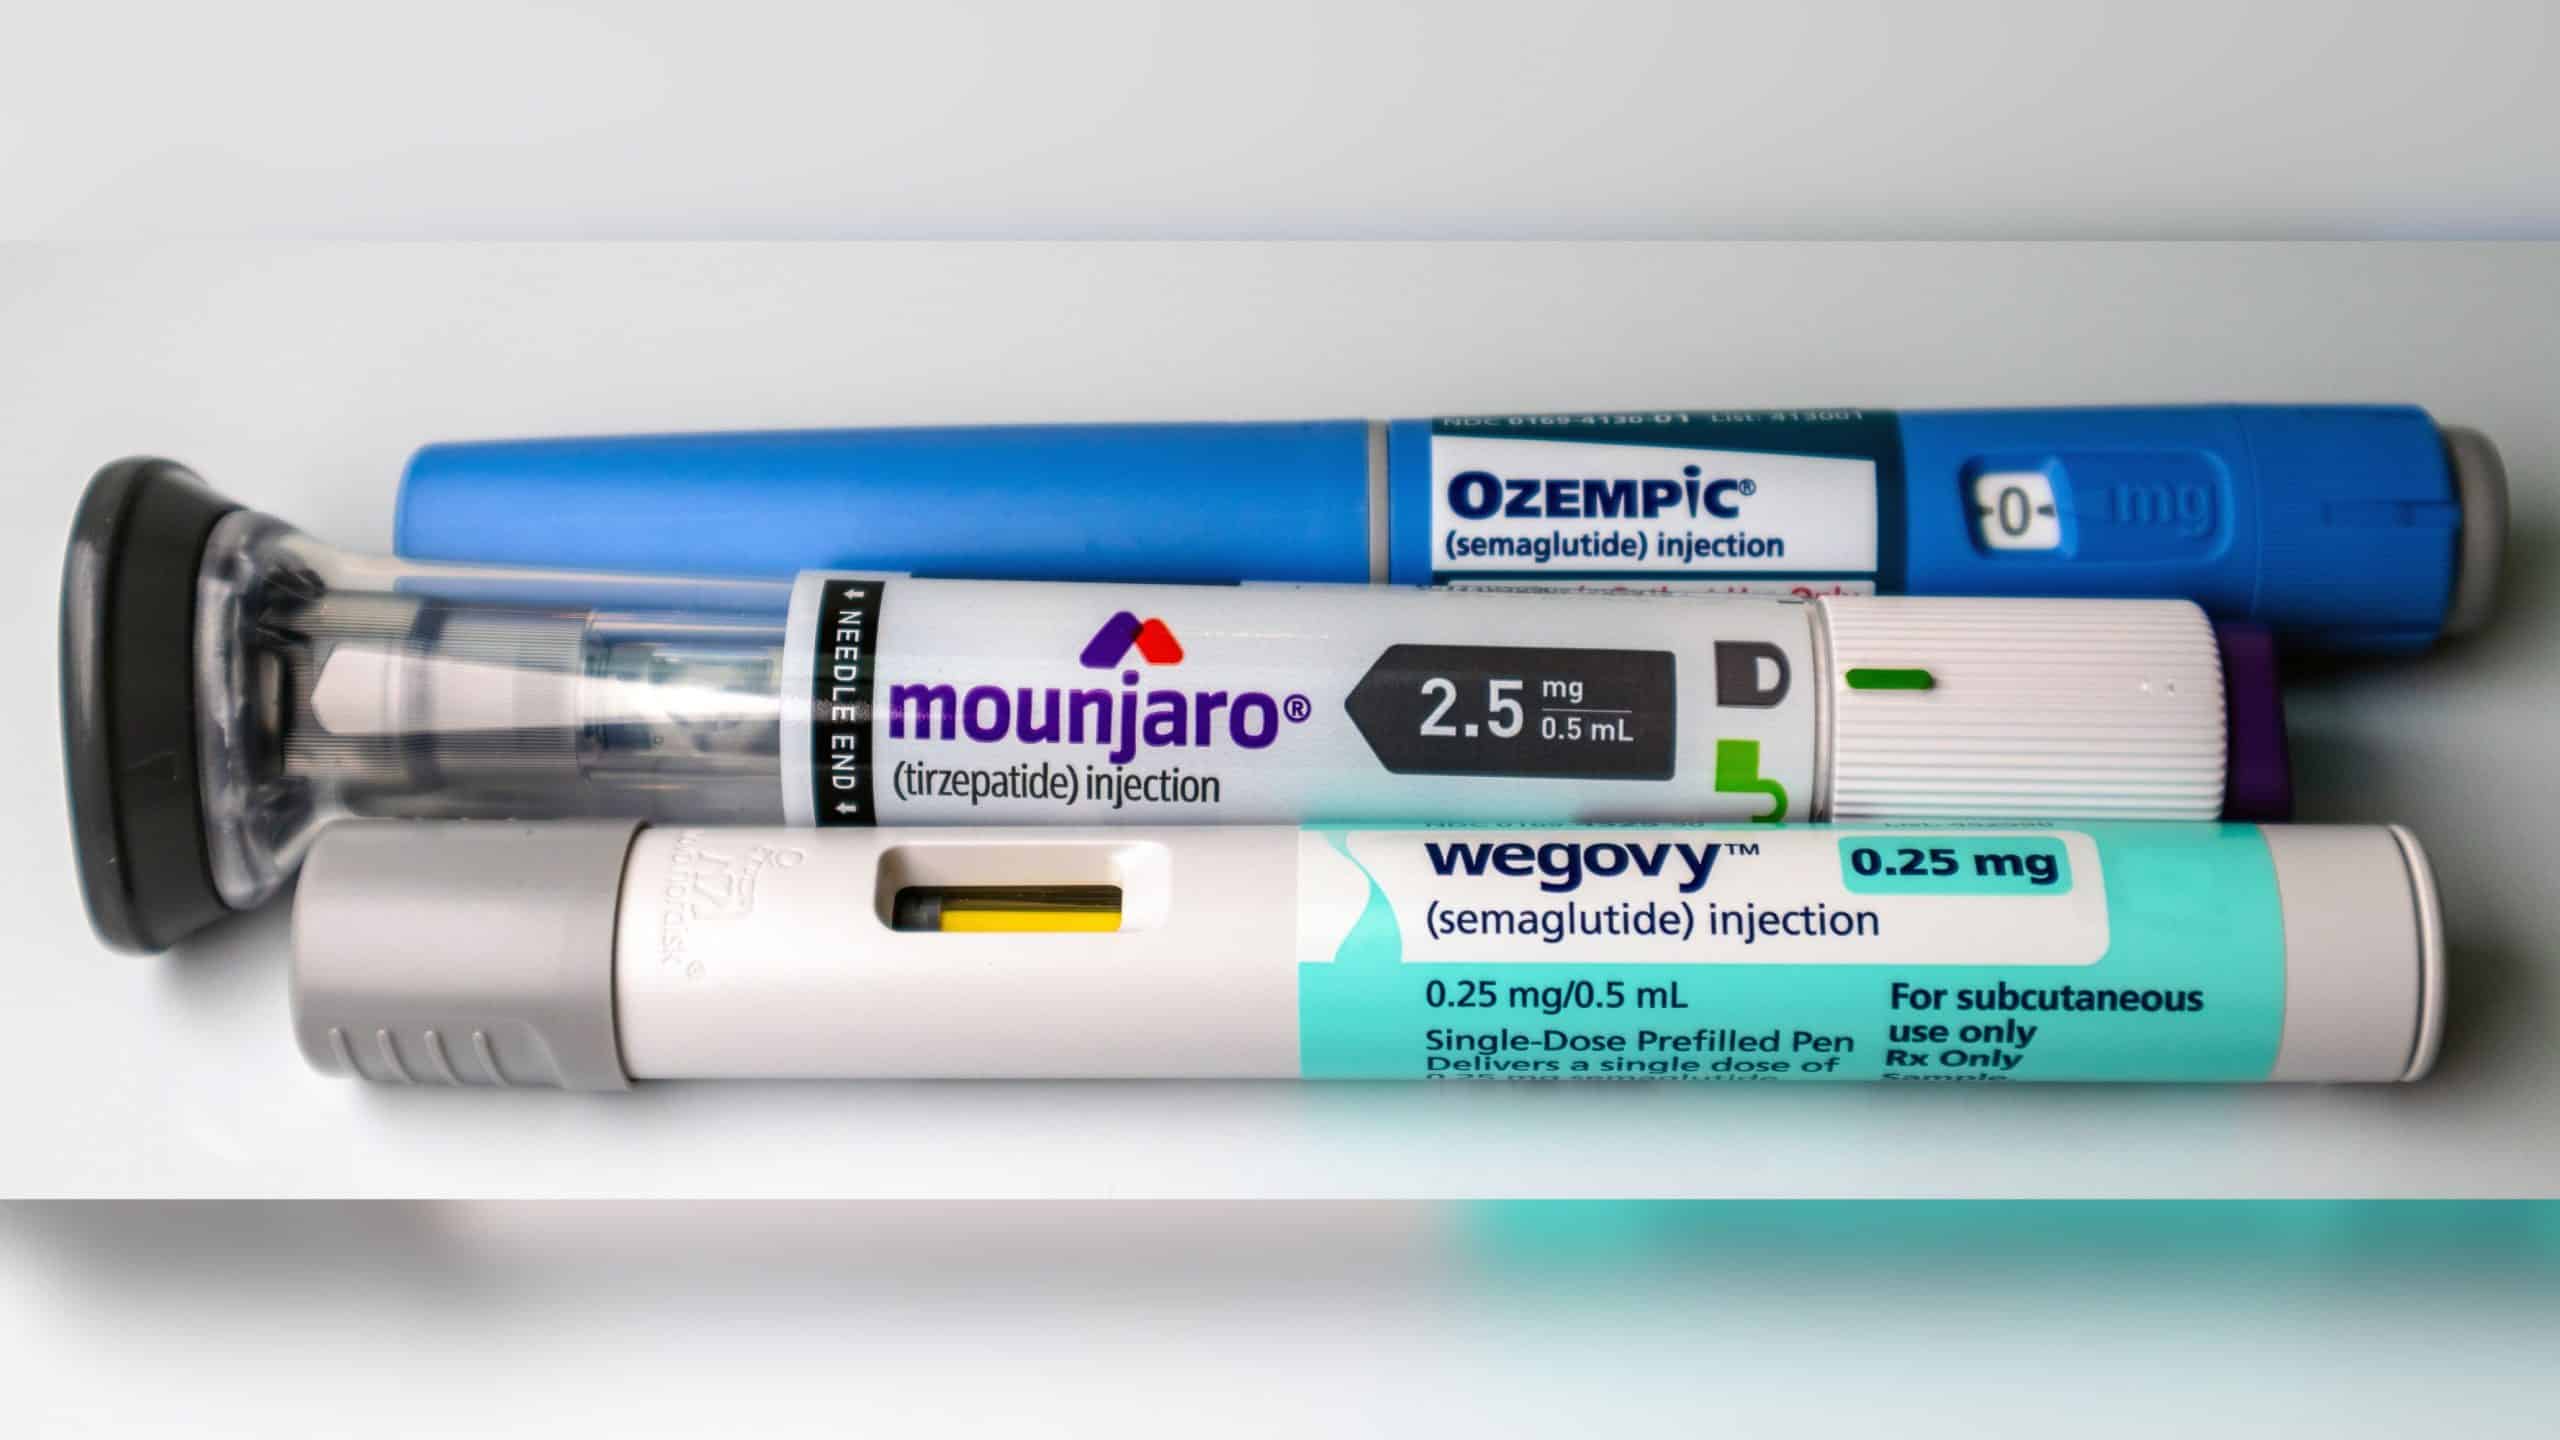

Ler maisOzempic e Mounjaro podem ampliar desigualdades, dizem cientistas

Medicamentos à base de semaglutida e tirzepatida, como Wegovy, Ozempic e Mounjaro, vêm transformando o tratamento da obe...

Ler maisOzempic e Mounjaro podem ampliar desigualdades, dizem cientistas

Medicamentos à base de semaglutida e tirzepatida, como Wegovy, Ozempic e Mounjaro, vêm transformando o tratamento da obe...

Veja os destaques do Olhar Digital News desta terça-feira: EMS anuncia preços da primeira caneta nacional de semaglutida...

Veja os destaques do Olhar Digital News desta terça-feira: EMS anuncia preços da primeira caneta nacional de semaglutida...